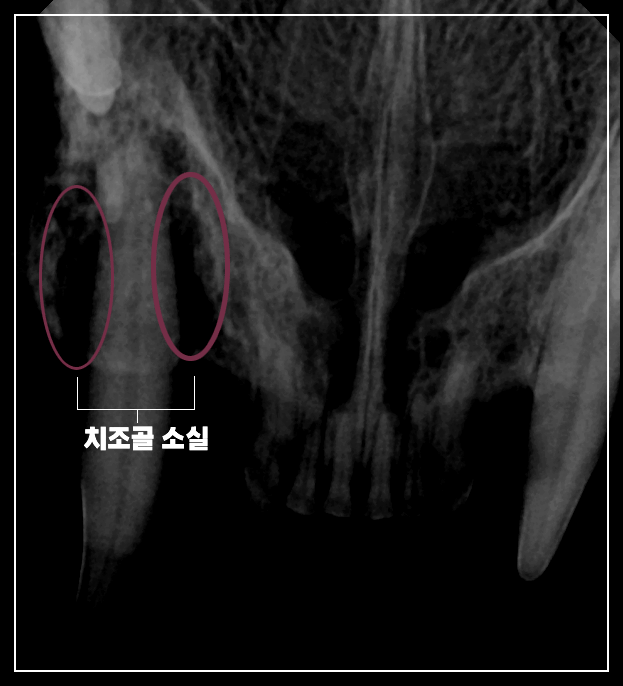

3. 치과 엑스레이 판독: 치조골 소실의 심각성

엑스레이는 고양이 치과 치료의 '나침반'입니다. 이번 사례의 엑스레이 영상에서는 어금니 부위를 중심으로 치조골(Alveolar Bone)의 소실이 뚜렷하게 관찰되었습니다.

치조골은 치아 뿌리를 턱뼈에 단단히 고정해 주는 역할을 합니다. 치주염 세균이 이 뼈를 녹이기 시작하면 치아는 마치 모래 위에 세워진 기둥처럼 흔들리게 됩니다. 이렇게 지지력을 잃은 치아는 단순히 '불편한 것'이 아니라, 신경이 노출되거나 주변 조직에 지속적인 감염원을 제공하는 '염증의 온상'이 됩니다.

본원에서는 엑스레이를 통해 보존 가능한 치아와 반드시 발치해야 할 치아를 명확히 구분하여 보호자에게 제시합니다. 이번 사례에서도 치조골 소실이 심한 어금니들은 통증의 원인을 제거하기 위해 발치를 결정했습니다.